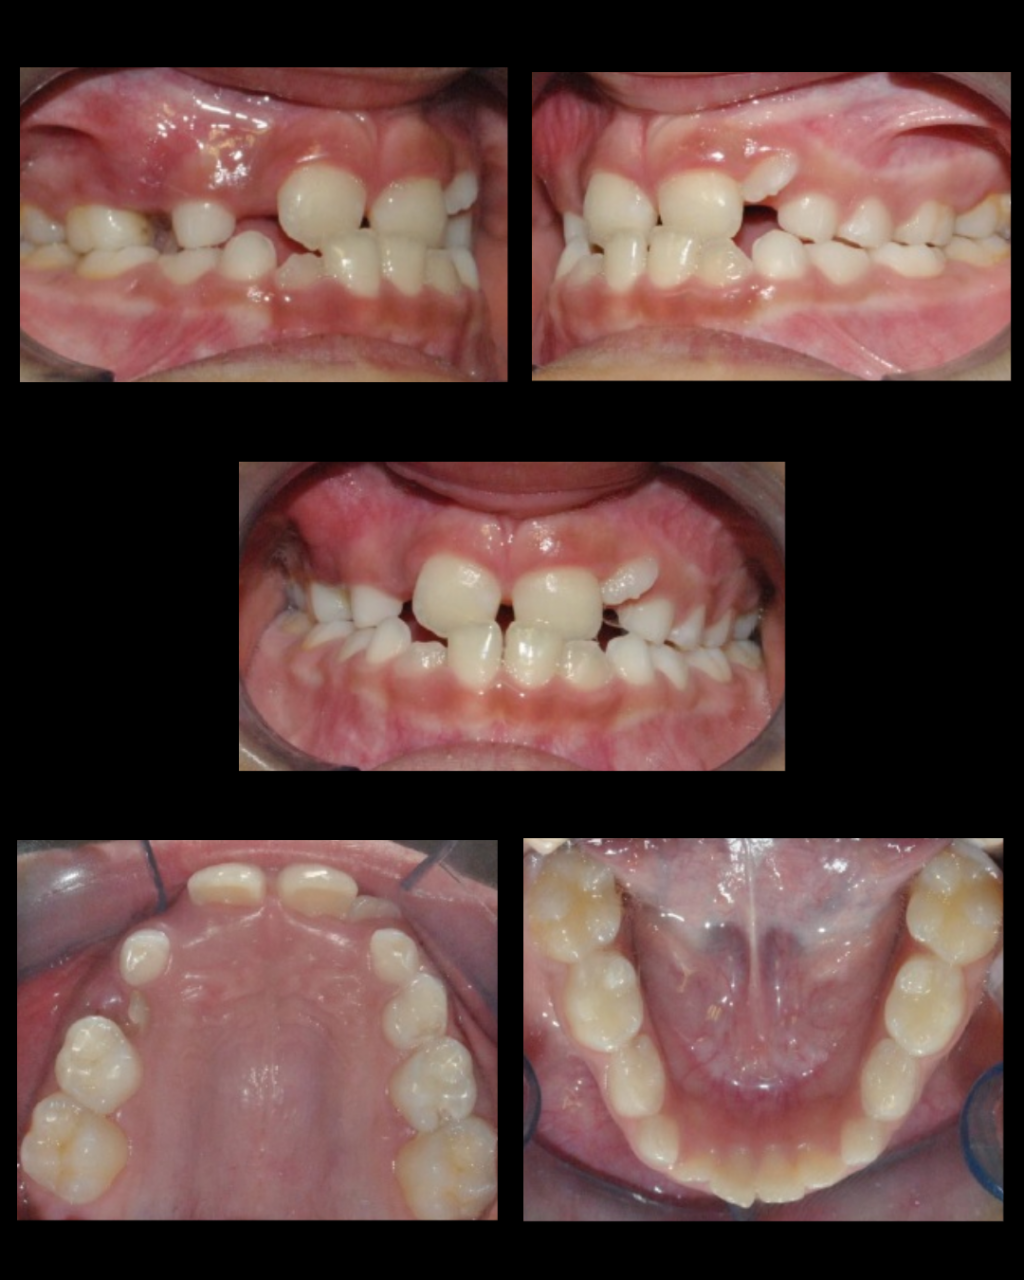

Trabajamos para construir una cultura cuyos valores primordiales sean el compromiso, con la atención centrada en el paciente y su familia. Además apostamos a la gestión del conocimiento, el bienestar y la seguridad de los pacientes.